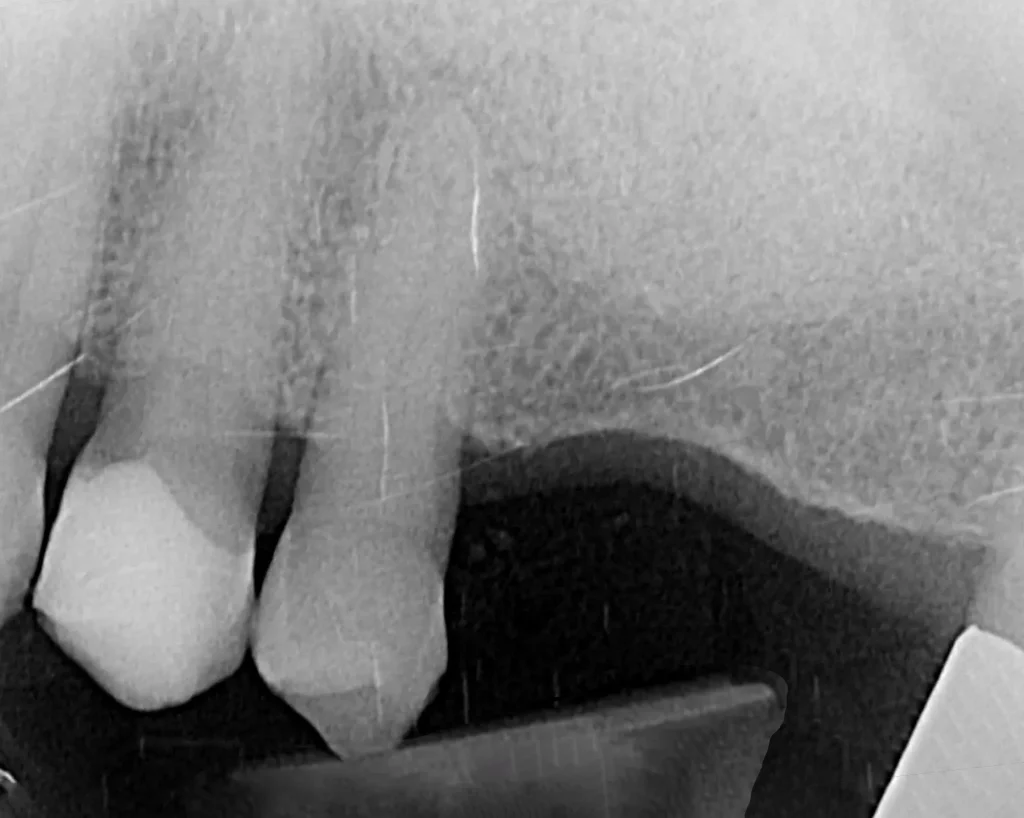

This lady attended Gentle after a previous implant had not worked. In the left photo below is a temporary bridge that kept falling out, which was frustrating for the patient, so she wanted to try again with implant treatment. Moreover, when she smiled, the adjacent eye tooth had an exposed root, so it looked too long. At the same time as placing gum around the implant, a gum graft was placed to cover the exposed eye tooth root. This improves the overall aesthetic outcome for the patient. Below on the right you can see how we took time to rebuild the bone and gum in the first phase of treatment, which gave the implant a solid foundation to sit in.

The implant was placed into the bone, under the gum, and a white post was chosen to fit into the implant to maximise the final crown’s appearance. The after photo was taken 5 years after the implant was placed and shows how nicely the work is performing.